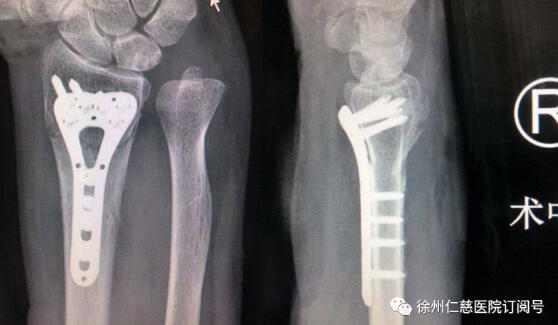

术中熊祖国医师用了微创手术,在其右腕内侧作了仅2厘米的切口,并用T形钢板内固定,手术很顺利,一小时完成。熊医师介绍,王老太手术后无需夹板等外固定,术后第二天就可以正常活动右手及右腕关节。